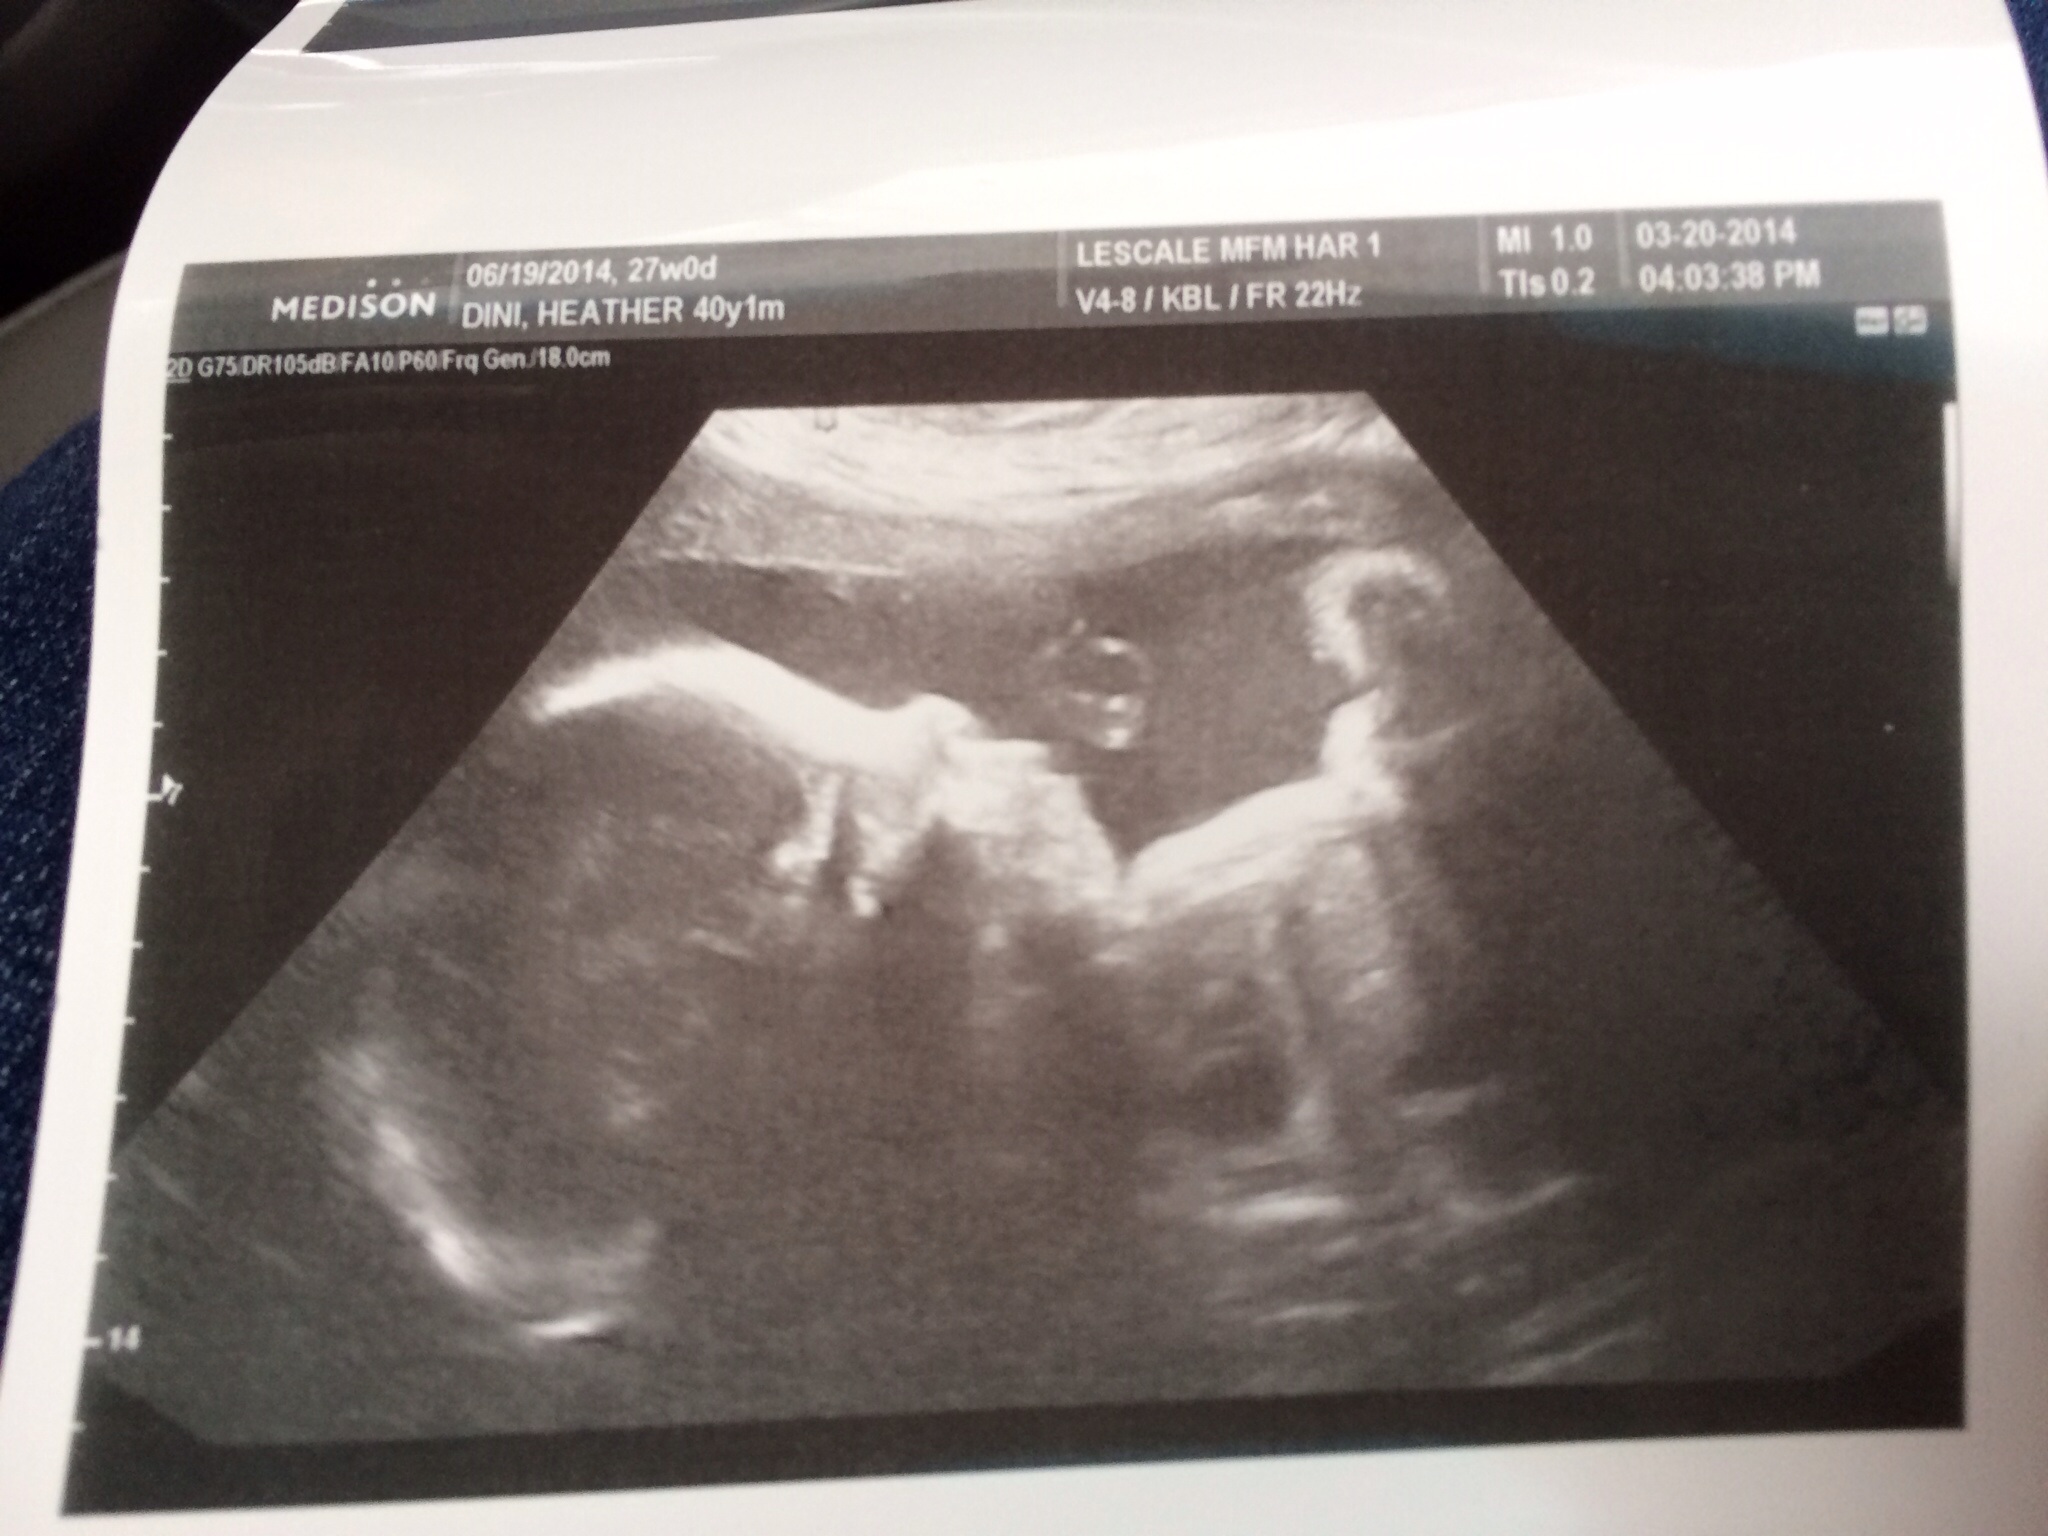

I just had to post. Had my US today. Checking to see if my placenta moved. It did!!

Baby is still breech but doing great!!

Here is the US and 3D US could not wait for the 3D. Super excited. My mom went with me. I'm her only child and I am 40. Lol